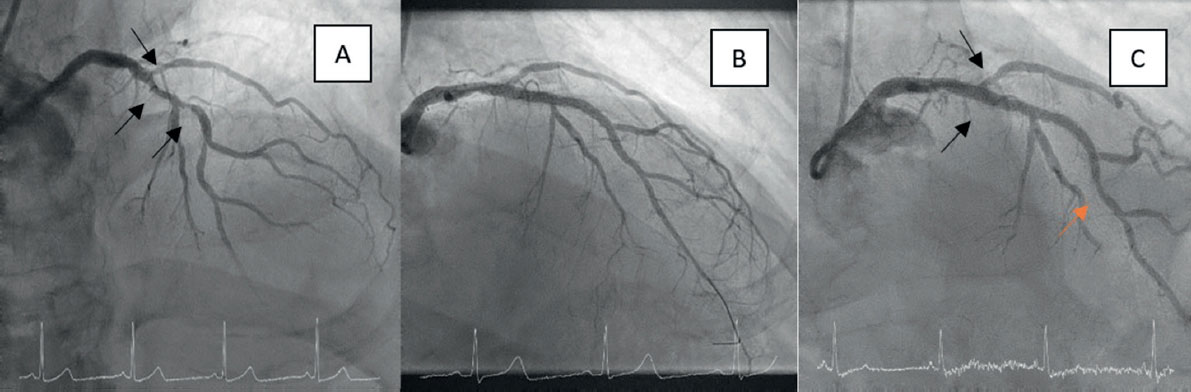

The rate of adverse events during follow-up is shown in table 3. After a mean of 3 years, 13 deaths were reported in the DCB group and 11 in the control group, mostly noncardiac. Among the 2 cardiac deaths reported in the DCB group, 1 was due to heart failure progression (after catheterization the patient underwent transfemoral aortic valve implantation and permanent pacemaker implantation), and the other was sudden death at home. No TLR, myocardial infarction, or definite lesion thrombosis occurred in the DCB group. A total of 8 myocardial infarctions were reported in the control group, although only 1 was not target-vessel related (right coronary revascularization in the context of a non-ST-segment elevation acute coronary syndrome). There was 1 case of TVR (figure 1) in the active group in a patient in whom the LAD-diagonal lesion was treated with orbital atherectomy due to severe calcification and who was readmitted 1 year later for unstable angina, without changes on electrocardiogram or echocardiogram and without enzyme elevation. However, repeat catheterization revealed progression of a lesion at the distal margin of the LAD stent, far from the bifurcation treated with DCB. This revascularization was not ischemia-guided, and the result at the bifurcation was optimal. The rate of TLR in the control group was 9.1%, with the MB responsible in 4 of the 8 cases, the SB in 2 cases, and both branches in the remaining 2. The rates of TLR and TVR were significantly lower in the DCB group (TLR, 0 vs 9.1%; P = .013; TVR, 1.2 vs 10.5%; P = .02). The logistic regression model (table 4) showed that none of the analyzed variables were independent predictors of events.

Figure 1. Single case of target vessel revascularization in the drug-coated balloon (DCB) treatment group. A: bifurcation lesion with severe calcification in the main branch. B: optimal result after orbital atherectomy, stent implantation in the left anterior descending coronary artery, and drug-coated balloon in the diagonal branch. C: 1-year follow-up result showing a significant lesion at the distal stent margin (orange arrow), far from the bifurcation treated with DCB (black arrows), which demonstrated sustained procedural success.